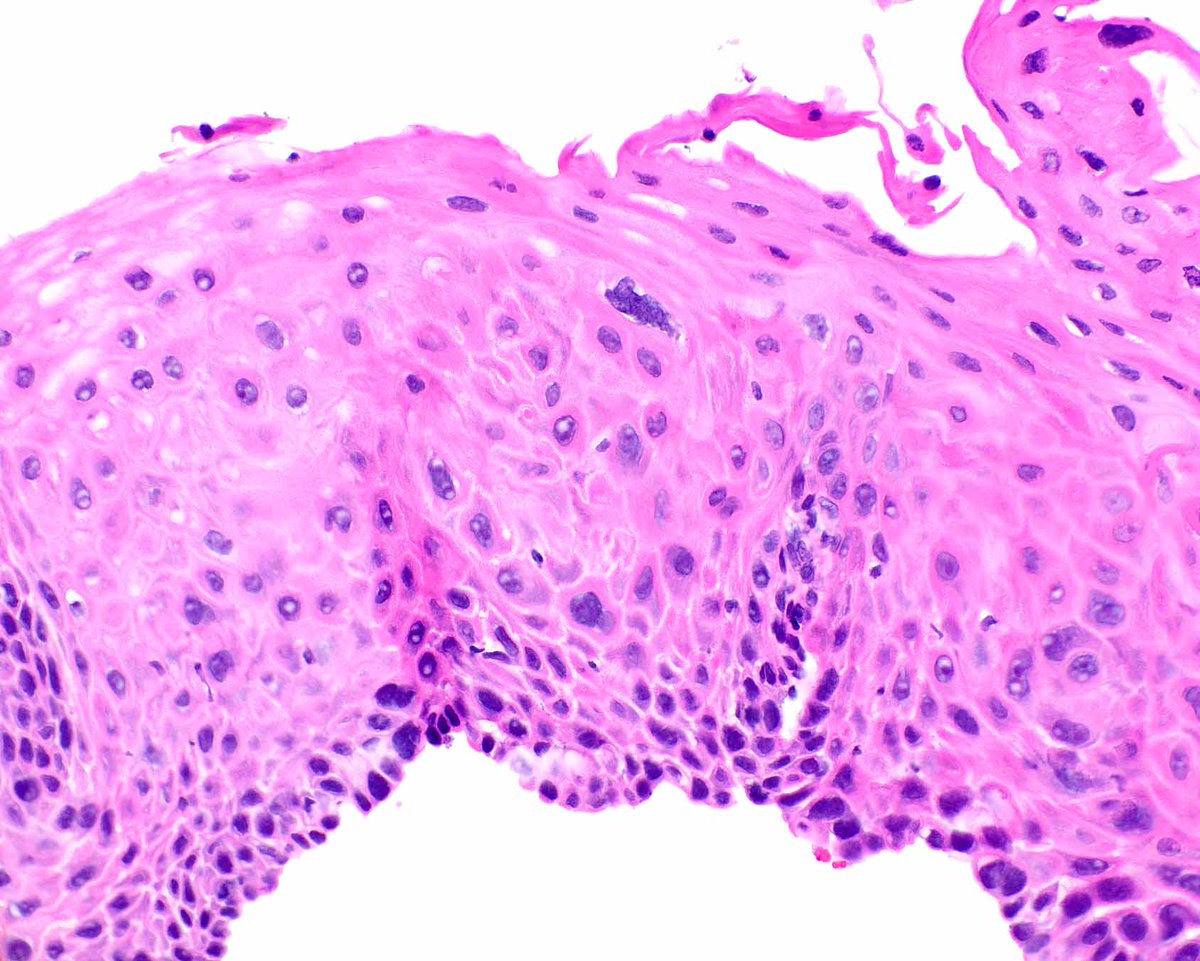

Adult male. Retroperitoneal mass. #PathX #PathTwitter #BSTPath

SumantaDas_7's tweet image. Adult male. Retroperitoneal mass.

#PathX #PathTwitter #BSTPath